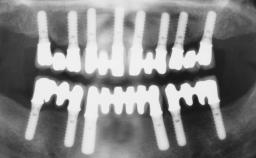

Rehabilitating an Edentulous Maxilla with a Fixed Dental Prosthesis Following Provisional Immediate Loading

This case features the flapless computer-guided placement of 7 bone-level implants, distributed to provide maximal support for the prosthetic framework. A rigid one-piece metallic framework was utilized as an interim restoration to reduce the risk of fracture associated with this prosthetic design. As part of the clinical examination, the SAC Assessment Tool was used, resulting in a surgical and restorative risk classification as “complex”.

# of Implants 7

Type of Implants Two-Piece

Guided Surgery Yes

SAC Level Complex

Defining Characteristics Fully edentulous upper jaw to be rehabilitated with four or more implants

Modality 6+ implants with immediate loading

Defining Characteristics Fully edentulous upper jaw to be rehabilitated with an implant-borne fixed dental prosthesis

Loading Protocol Immediate